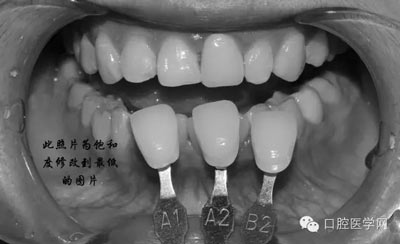

1、術(shù)前比色照

將比色照飽和度調(diào)到最低有助于牙齒明度的選擇

將比色照的飽和度調(diào)到最高有助于牙齒道飽和度選擇